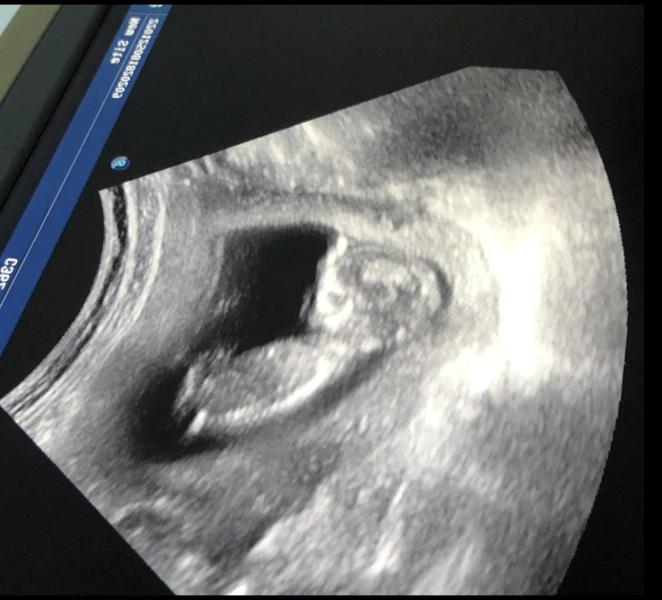

Сравнение животиков на 13 неделе беременности: первая и вторая

post image 1

милые моменты ❤️ на первом фото беременность сейчас, а на втором первая бер. оба в 13 недель ❤️

пол не видно сказали, но я хочу девочку 😂